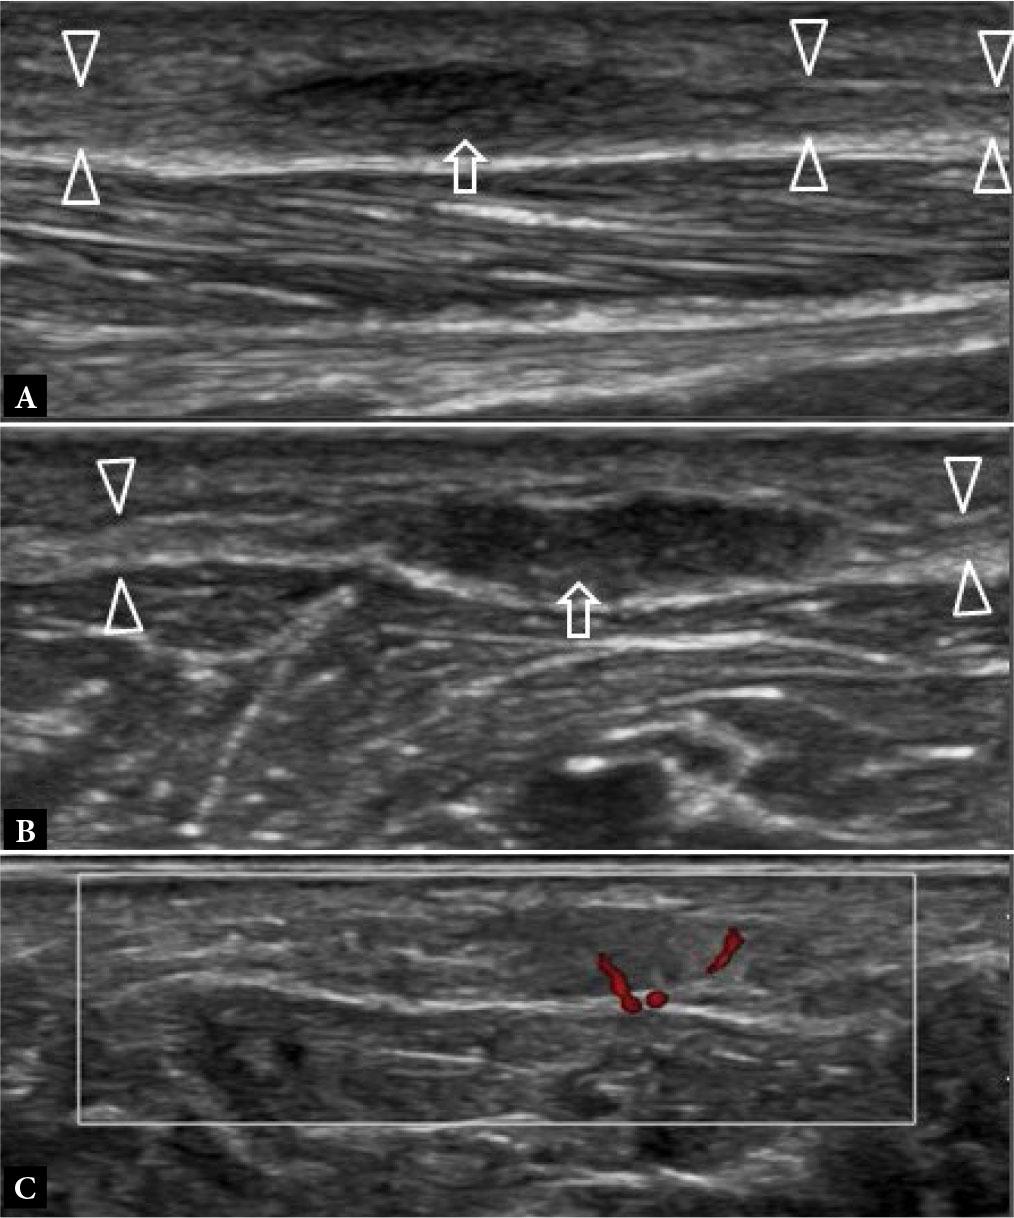

Stress fractures typically occur in young to middle-aged individuals undertaking unaccustomed high levels of exercise over an extended period. The 2nd and, less frequently, the 3rd metatarsal mid-shafts are commonly affected sites(1) (Fig. 1). The base of the 2nd metatarsal is splinted between the distal end of the medial cuneiform and the 3rd metatarsal bone. It is also a key weight-bearing bone, making it more susceptible to injury. The 1st, 2nd and 5th metatarsal bases, the navicular, cuneiform, cuboid, and medial sesamoid bones are additional common sites of stress fractures in the mid- and forefoot(1,2) (Fig. 2). Radiographs are normal in the earliest stages of stress fracture. US at this juncture may reveal a cuff of echogenic thickening due to thickened periosteum (‘periostitis’) around the cortex of the affected bone area. The cortex may be less distinct than usual, together with juxtacortical soft tissue edema and hyperemia (Fig. 1). While such findings are non-specific, they are usually diagnostic in the appropriate clinical setting without the need for additional imaging other than radiographic follow-up. MRI will provide even earlier detection of stress fracture than US, revealing focal bone marrow edema (BME) at the affected site, often with a thin hypointense fracture line(1) (Fig. 2). In the appropriate clinical setting, BME on fat-suppressed, fluid-sensitive sequences without a visible fracture line is termed a ‘stress reaction’ rather than a ‘stress fracture’(1). Radiographs and US will typically be normal in stress reaction. It is important to correlate any BME with clinical symptoms, as BME may occur due to physiological bone remodeling without necessarily being reflective of an injurious stress reaction(3).

Fig. 1.

41-year-old female with forefoot pain and swelling for one month. There was no specific traumatic event and no undue sporting activity. A tendon injury was suspected clinically A. Dorsoplantar (DP) radiograph shows normal 2nd metatarsal bone (arrowhead). B. Longitudinal greyscale and C. color Doppler, and D. transverse greyscale US images show moderate severity localized periosteal thickening (open arrow) of the 2nd metatarsal shaft dorsally, with moderate adjacent soft tissue thickening (open arrowhead) consistent with active stress fracture. E. Radiograph three months later showed marked periosteal thickening of the 2nd metatarsal shaft (arrow) compatible with healed stress fracture